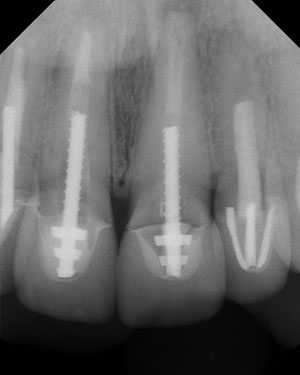

Front Tooth Implants

The front tooth implant is the most difficult and challenging implant procedure. Our practice has focused on this procedure for more than 25 years, and we have handled thousands of these type of cases. We have published scientific papers and presented lectures throughout the U.S., Canada, and Europe on this subject.

The key is an organized, “one step at a time” approach that concentrates on soft tissue position and bone health. It also requires us to work with your dentist to optimize esthetics.

We have performed a number of cases. The picture you see is 14 years after placement.